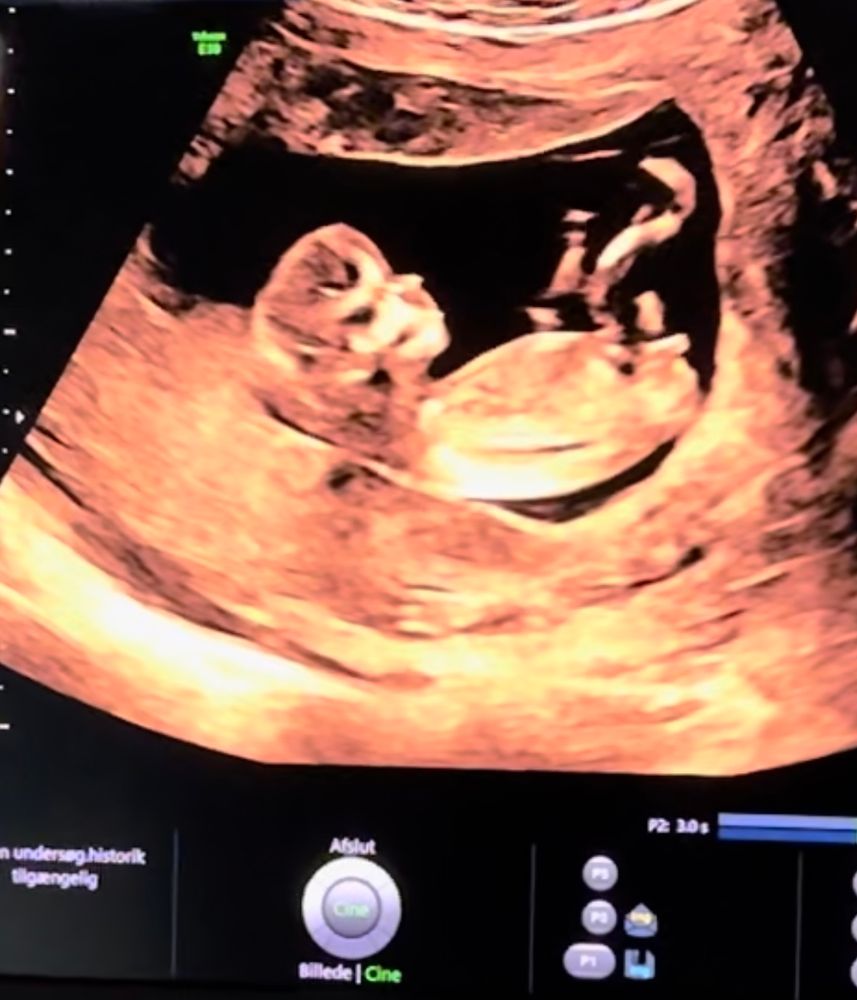

УЗИ 12 недель 😍

УЗИ, КТГ, доплерПривет всем! Сегодня ходила на первый скрининг 💕 здоровенькие и все хорошо 🙏❤️

Не могу разобраться где у малыша половой бугорок, я так понимаю он скрестил ноги. И периодически прыгал. Но есть скриншоты с видео.

Публикую для голосования, кто там 😅❤️